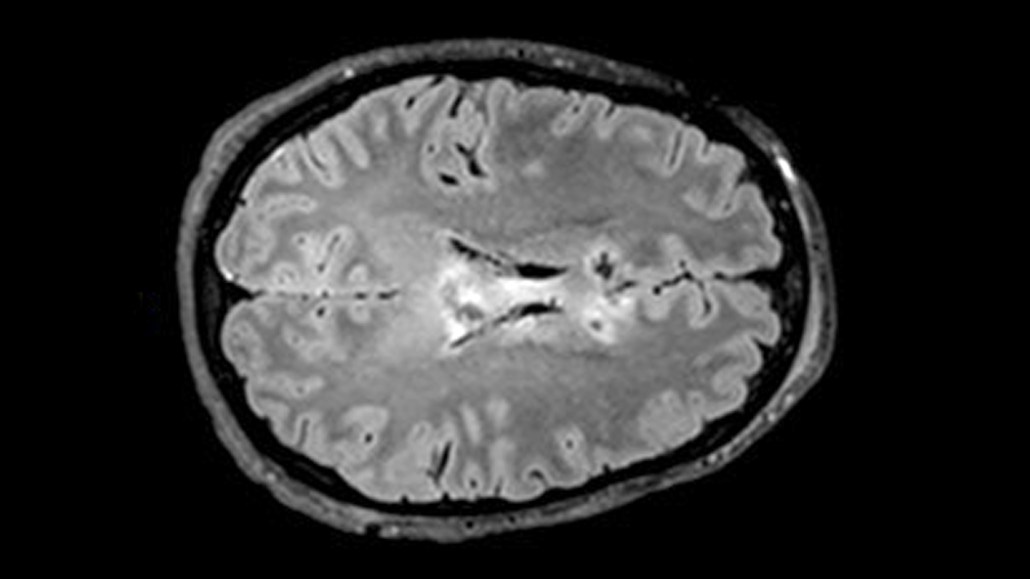

The fatty material surrounding fibers that send signals between neurons degenerates after a traumatic brain injury. A new study pinpoints a blood biomarker that can predict this damage.

Living Art Enterprises/Science Source